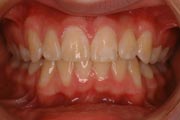

Crowding

After